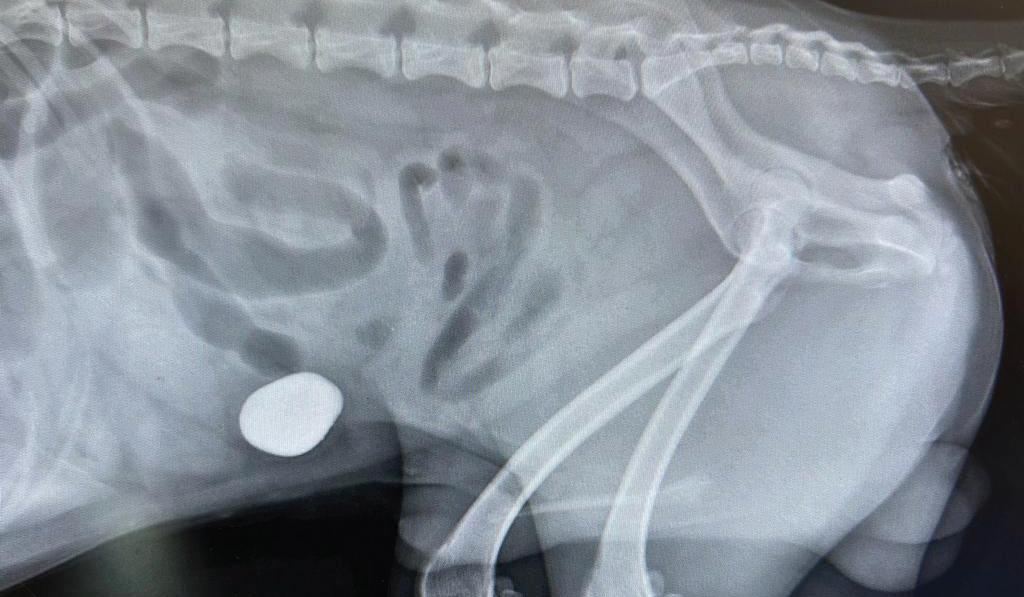

Foreign bodies in pets

LIKE toddlers, pets have a tendency to chew anything they can get into their mouths. This becomes a serious and potentially life-threatening problem if the objects are swallowed. We have seen various ‘foreign bodies’ ingested by pets which include toys, clothing, mango seeds, rocks and socks!

Recently, Kyza the Schnauzer was presented to the clinic, generally not feeling well. He was not eating and soon began vomiting. An x-ray revealed a foreign body in his intestine, causing a partial obstruction. After being stabilized with IV fluids/ electrolytes, pain relief and antibiotics,

Kyza underwent exploratory surgery. Dr Camille & Dr Lesca removed a rock from his inflamed and traumatised intestinal tract.

The digestive tract is essentially a long tube, passing food from the mouth, down the oesophagus, into the stomach, through the lengthy small

intestine, then forming a stool in the colon and out the rectum. It generally takes the foreign body from 10-24 hours to move through the entire digestive tract. Some objects, however, can actually remain in the stomach for longer periods of time, even months.

When objects are too large to pass, they usually obstruct at the stomach outflow or within the small intestine itself. With linear foreign bodies, the continual movement of the intestinal tract can literally bunch the intestines into an accordion-like mass.

Kyza remained in intensive care on i/v fluids until he was able to digest a special diet

If you suspect that your pet has swallowed a foreign body, call Orchard Hills Veterinary Hospital immediately. The sooner your pet receives medical attention, the better his or her chances of full recovery with fewer complications.